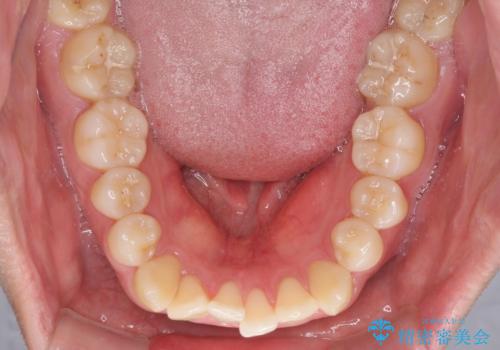

インビザラインで奥歯の咬み合わせと前歯のデコボコを改善

- 前歯のデコボコと奥歯の咬み合わせを気にして来院された患者様です。

前歯のデコボコはインビザラインで十分に対応可能と判断できましたが、咬合力が強いため、臼歯(特に右側)の交叉咬合はインビザライン単体では困難と思われました。

インビザライン単体では右側の交叉咬合を解消することができなかったため、アンカースクリューを併用して咬合を改善させました。